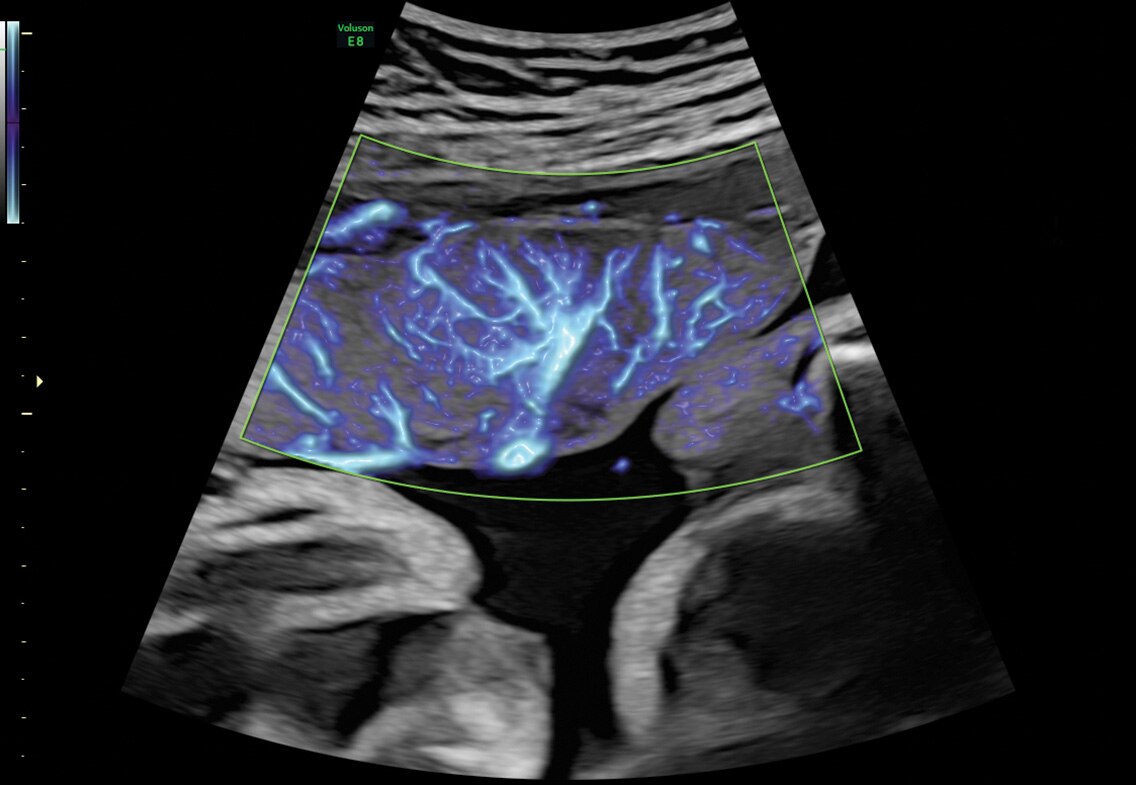

SlowflowHD

Expanda o intervalo do fluxo sanguíneo visível para incluir velocidades baixas com o SlowflowHD™ para visualizar a perfusão sanguínea em vasos muito pequenos.